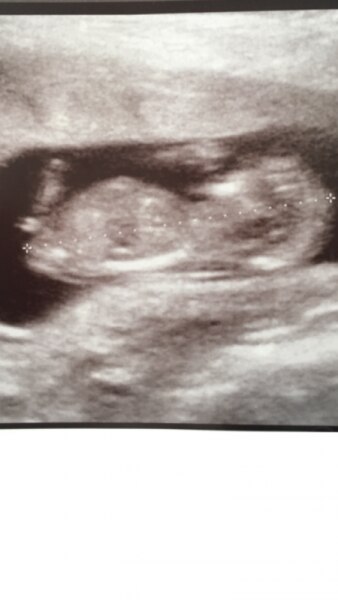

Hallo liebes Forum ich bin über diese Nub Theorie gestolpert und habe bei 12+5 ein US gehabt. Könnt ihr mir helfen - Sieht das nach Junge oder Mädchen aus ;) LG Franzi

Bild zu Nub Theorie - wird mein Baby ein Junge oder Mädchen - Schwanger - wer noch? Rund um die Schwangerschaft

Spontan würde ich Junge sagen...aber bin ja kein Profi

danke für deine einschätzung! ich bin iwie unsicher da der winkel ja glaube ich kleiner ist als 30 abet die spitze am ende des nub is vielleicht bisschen höher :) gibt es noch weitere einschätzungen? unf ist die nub theorie sicher? lg franzu